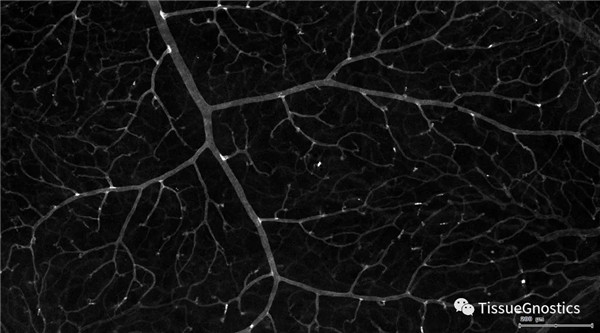

單通道灰階圖(↑:FITC,↓:Texa Red)

血管識別:根據(jù)Texa Red通道進(jìn)行識別,并去除面積小的及非同一焦面的血管,僅對確定的清晰的同一焦面的大血管進(jìn)行面積統(tǒng)計(jì)。

血管與小膠質(zhì)細(xì)胞的距離

血管與小膠質(zhì)細(xì)胞的距離0-0.1μm(紅色框線標(biāo)記)

血管與小膠質(zhì)細(xì)胞的距離0.1-1μm(粉色標(biāo)記)

血管與小膠質(zhì)細(xì)胞的距離1-3μm(粉色標(biāo)記)